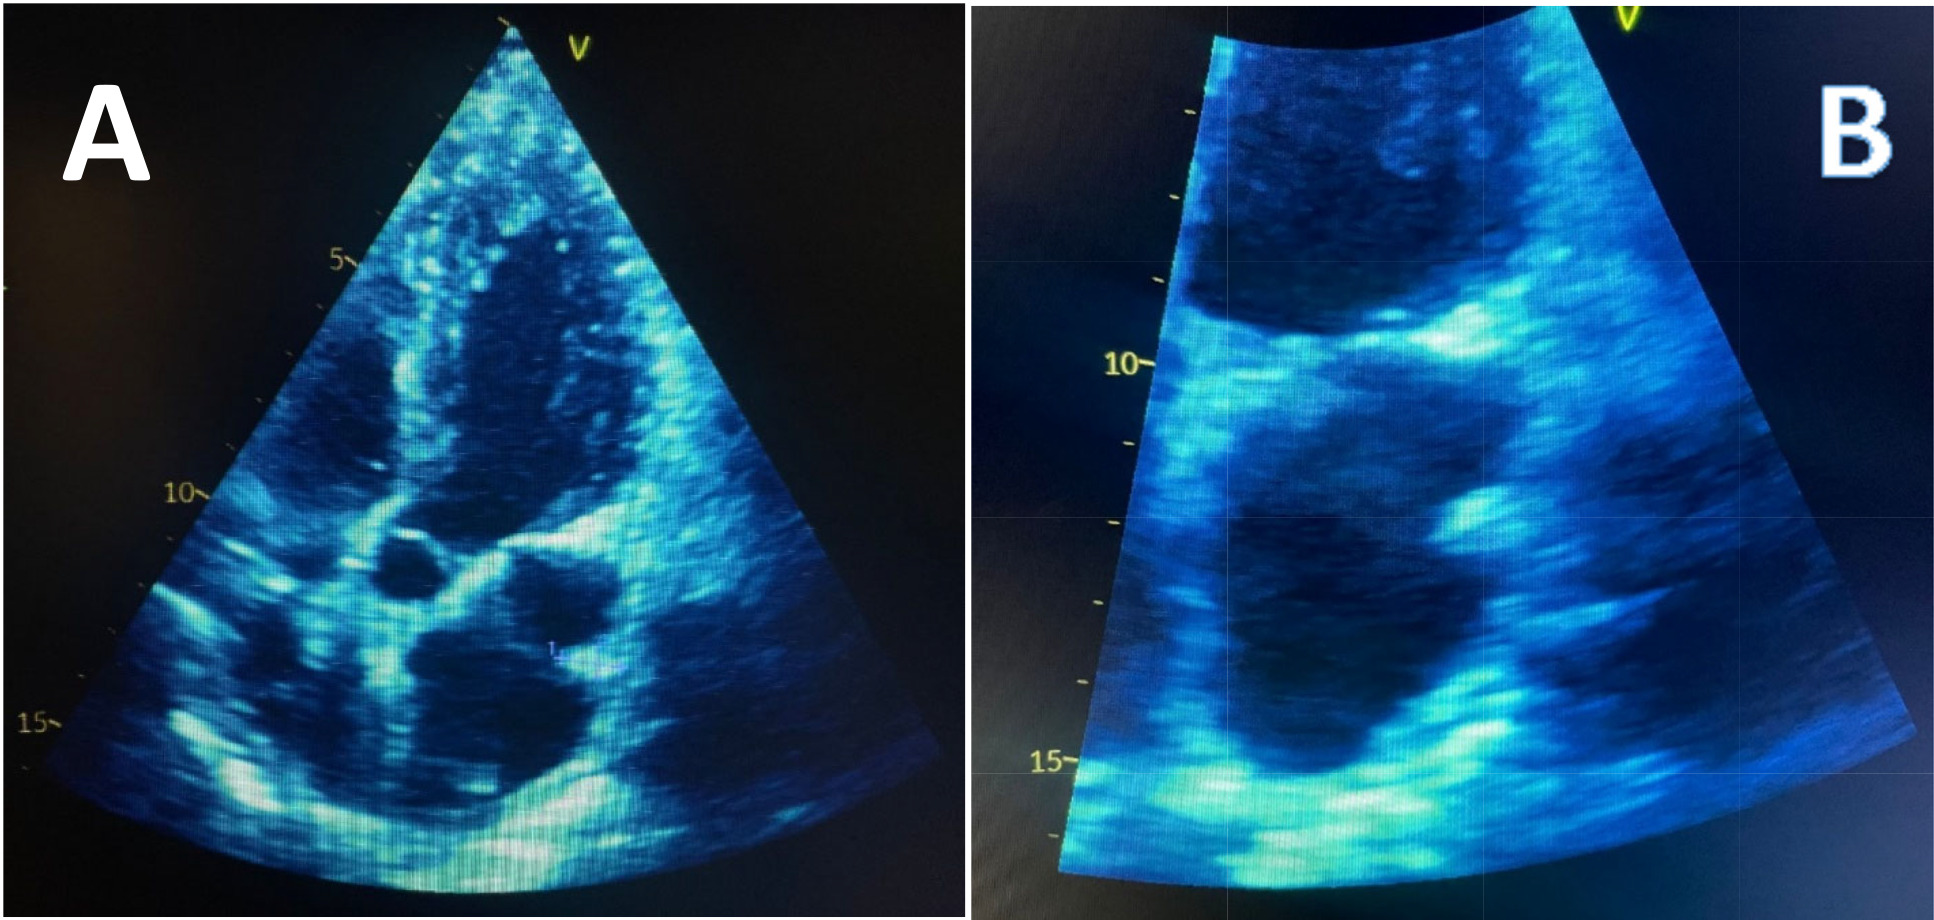

Physical examination showed blood pressure 110/60, pulse of 57bpm, and respiratory rate of 17 per minute. There was no jugular venous distention, well-ventilated lungs, normal cardiac sounds, no murmurs, and lower limbs without edema. The lipid profile was normal. An electrocardiogram was performed that showed sinus bradycardia with 57 bpm (Figure 1). Chest X-ray did not have any notable findings. A transthoracic echocardiography was performed. In the 4-chamber view, at the entrance of pulmonary veins, a pedicled hyperechoic image approximately 11x6mm projecting towards the lateral wall of the left atrium, corresponding to Coumadin ridge was identified (Figure 2). Her episode was ultimately attributed to anxiety, and her medications were discontinued. She was advised to start lifestyle changes and given a referral to psychiatry. CT Brain was not done since the patient did not present with any neurological signs at the time of physical examination and she only had transient right sided weakness lasting 15 minutes.

Echocardiogram has drastically improved in terms of clarity and resolution and can now identify normal anatomical variants of the heart. The ridge may appear to be attached to the roof of the left atrial appendage with a rounded end extending towards the atrium, and often referred to as “Q-tip sign” on echocardiography.1 Due to its rounded edge, the coumadin ridge has often been falsely diagnosed as a thrombus, thereby, resulting in unnecessary anticoagulation with Coumadin (warfarin) and hence the name, “Coumadin ridge”.2 It is an embryological remnant similar to a band in the left atrium between the left upper pulmonary vein and the left atrial appendix, and is considered an anatomical variant, and if particularly prominent, it may be easily mistaken for a tumor such as an atrial myxoma or thrombus.3,4 The ridge contains the Marshall ligament, the autonomic nerve bundle and small artery of the atrial node, and noted to be more common in patients with atrial fibrillation.5,6 If coumadin ridge is seen on TTE and questions still remain about the diagnosis, a full-volume three-dimensional transthoracic echocardiography with color Doppler can provide additional clarity of the surrounding structures.7 Transesophageal echocardiography can also be performed, if necessary, as the Coumadin ridge is best seen using the midesophageal two-chamber view.7 In very difficult cases, a cardiac MRI can be done to provide clarity to the diagnosis. On both T1 and T2 weighted images, the Coumadin ridge should have the same signal strength as the adjacent cardiac tissue.3 In conclusion, coumadin ridge is a normal variant of the left atrium, and awareness of this diagnosis is essential to avoid putting patients through unnecessary interventions, both treatments and surgeries.